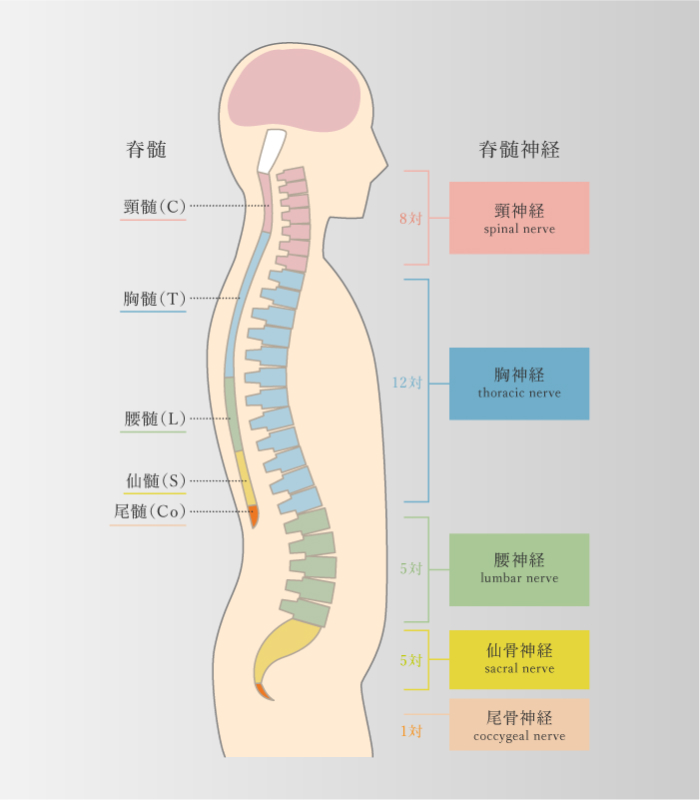

脊柱管狭窄症(神経根型/馬尾形)

-

柱管内部の変性が原因

- 腰部神経組織周囲が変性や肥厚することにより神経を圧迫する

- 間欠性跛行(閉塞性動脈硬化症との鑑別)

頸部の神経症状

頸部の神経症状

-

頸椎ヘルニア

-

椎骨間にある髄核が飛び出し、脊髄や神経根を圧迫して痛みなどが生じる

頸部椎間板症

-

髄核がずれ、線維輪に亀裂が入る痛みが生じ、その状態が続くことによって徐々に椎間板の水分が減少して変性を起こし、機能が低下する

頸部神経根症

頸部神経根症

-

首の骨に負荷が継続的にかかり続けることで椎間板が変性し、骨棘を形成することよって、頚椎にある「椎間孔」が狭くなり、神経根が圧迫された刺激されて肩や腕の痛みや痺れといった症状をきたす。